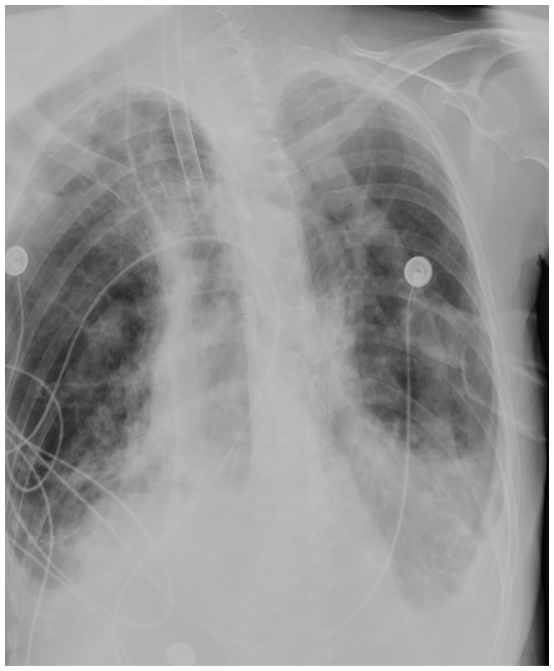

5月8日晨交班:患者镇静、镇痛状态,经口气管插管接有创通气,去甲肾上腺素维持血压,呼吸机压力控制模式,氧浓度45%,PEEP 5 cmH2O,呼吸频率18次/min,PC 16 cmH2O。心电监护示:脉搏75次/min,呼吸18次/min,血氧饱和度94%,血压93/59 mmHg。晨起血气分析:pH 7.412,PaO71.1 mmHg,PaCO2 75.4 mmHg,Lac 1.7 mmol/L。复查床旁胸片示:两肺透亮度较前明显好转,尤其是双下肺(图4)

图4  患者床旁胸片(2024-05-08)